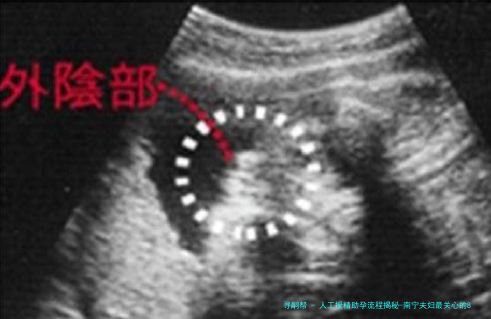

术前检查费(约2000-3000元):夫妇双方需要进行全面的身体检查,女性检查囊括妇科超声、内分泌激素测定等,男性便要进行精液常规解析等,以确保体质状况适合进行人工授精。